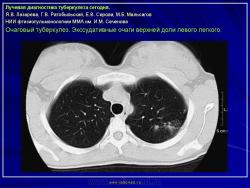

Лучевая диагностика туберкулеза сегодня

Я.В. Лазарева, Г.В. Ратобыльский, Е.В. Серова, М.Б. Мальсагов

НИИ фтизиопульмонологиии ММА им. И.М. Сеченова